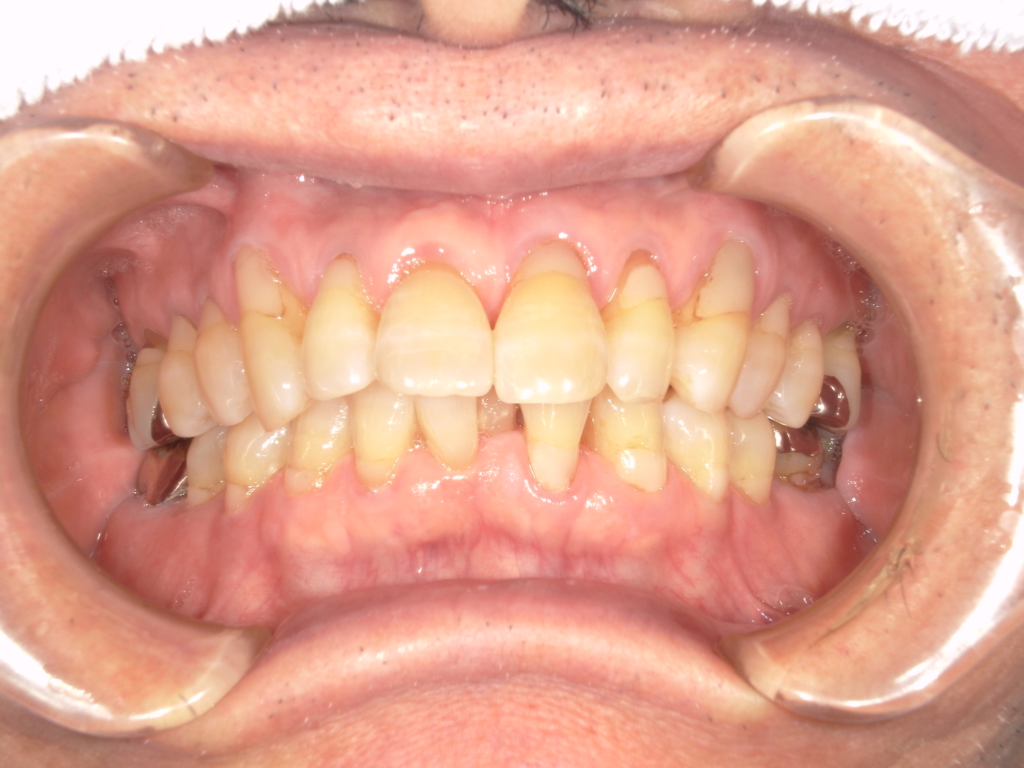

Y様インプラント実例 #44

左の上下の奥歯をインプラントで治療しています。

左下の奥歯は歯を抜くのと同時にインプラントの埋め込みを行っています。

被せものは上下、セラミックスで作っています。

治療前

治療後